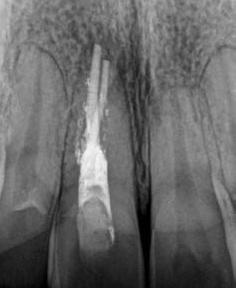

Egy 38 éves nőbeteg a korábban kezelt jobb felső második kisőrlőfogából (1.5) kiinduló mérsékelt fájdalom miatt jelentkezett rendelésünkön. A kórtörténetében jelen panasza szempontjából releváns információ nem szerepelt. A beteg a klinikai vizsgálat során vertikális kopogtatásra enyhe érzékenységet jelzett. A kérdéses fog körül mérhető szondázási mélység és a fogmobilitás fiziológiás volt. Periapicalis röntgenfelvételen egy, a fog gyökércsúcsán túl presszálódott betört gyökérkezelő műszerből származó eszközfragmentumot láttunk (2. a. ábra). A preoperatív CBCT-felvétel a buccalis csontlemez épségét igazolta (2. b-c. ábra). A fog revíziója öt hónappal korábban történt. A már előzőleg gyökérkezelt, gyökértömött, majd revideált 1.5-ös fog esetében a diagnózisunk periodontitis periapicalis symptomatica volt. A periapikális elváltozás kezelése érdekében navigált endodonciai mikrosebészeti beavatkozást végeztünk.

gítségével tovább módosítottuk. Az így kapott sebészi sablon egyértelműen meghatározta a periapikális terület eléréséhez szükséges csontablak határait (2. e-f. ábra) Helyi érzéstelenítést követően teljes vastagságú mucoperiostealis lebenyt képeztünk, majd a buccalis csont feltárását követően (2. g. ábra) a sablon segítségével bejelöltük a preparálandó csontablak határait (2. h. ábra). A csontablak kialakítása során Piezotome CUBE LED kézi-darabot alkalmaztunk, majd a leemelését követően a betört eszközt megkerestük (2. i. ábra) és eltávolítottuk (2. j. ábra). A rezekciót ultrahangos megmunkáló fejekkel (ACTEON) végeztük, majd retrográd preparáció következett.

A retrográd gyökértömés elkészítése során TotalFill BC RRM Fast Set Putty-t (FKG) használtunk (2. k. ábra). A lebeny széleit 5/0-s Prolene varratokkal egyesítettük (2. l. ábra). A varratok a műtétet követően 72 órával kerültek eltávolításra. A beteg két évvel később kontrollröntgen készítése céljából érkezett rendelőnkbe. A vizsgálat során a fog tünetmentesnek és funkcióképesnek bizonyult (2. m. ábra).